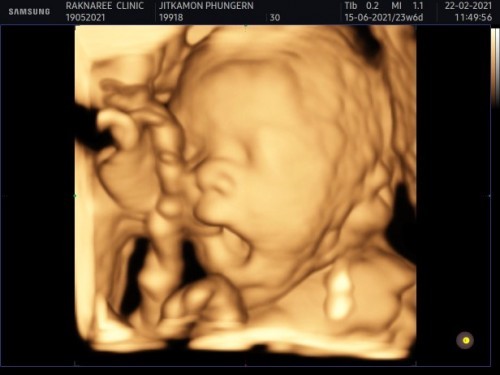

ผู้ชายค่ะ กำหนดคลอด 15มิถุนายนค่ะ